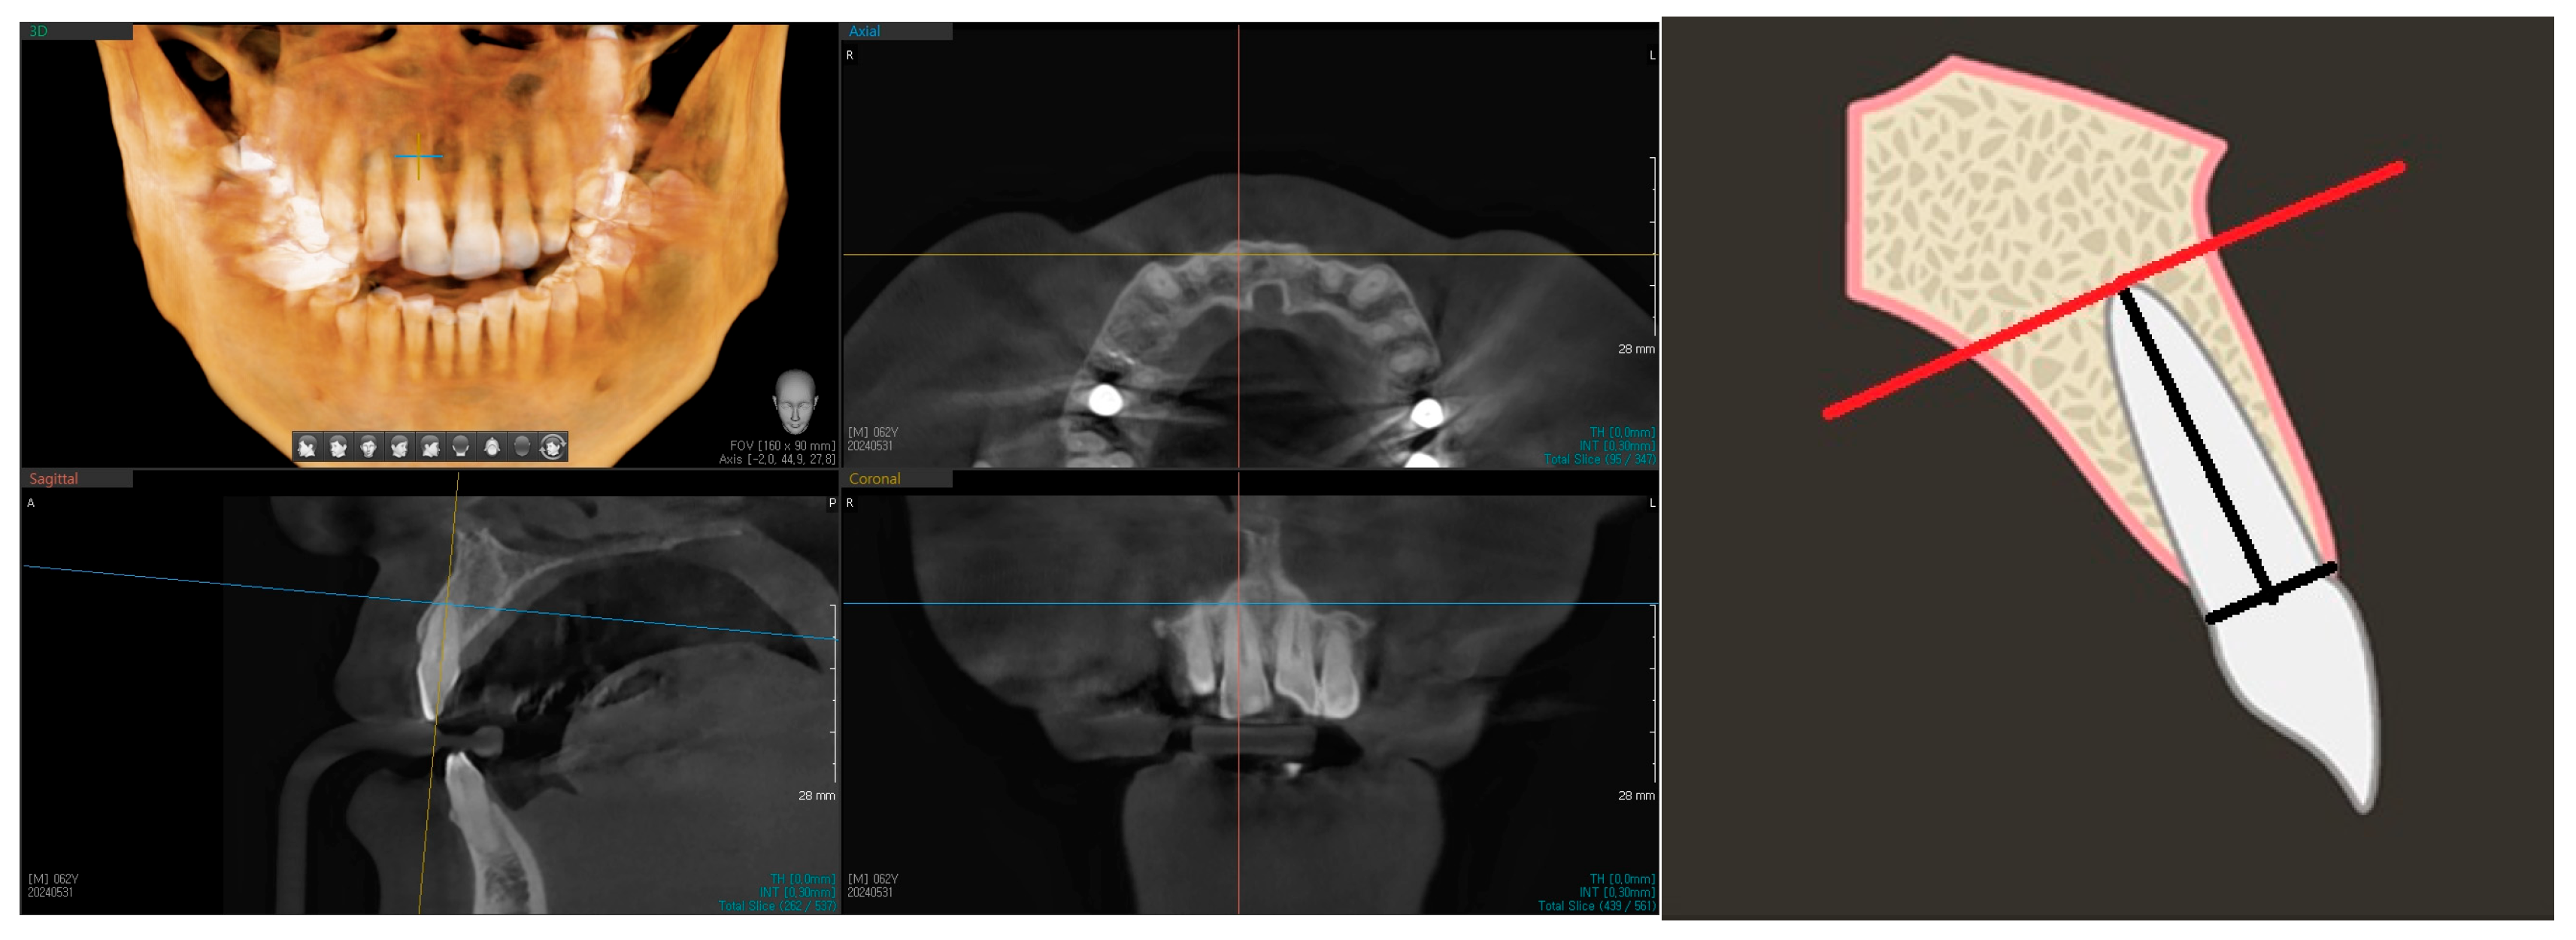

Landmarks (central incisor root apex, anterior IC wall, and buccal alveolar bone) were identified and marked in the software before the measurements were performed. The sagittal section of the chosen incisor was viewed at the center of its mesial-distal dimension (Figure 1). The long axis of the tooth was marked by the midpoint of the line drawn from the buccal enamel–dentine junction to its palatal counterpart, the apex of the root. The long axis of the tooth root, instead of the long axis of the whole tooth, was used because the range of the crown-root angle is known to be 25.5 degrees for maxillary central incisors [16,17]. From this reference line, a perpendicular line was drawn from the apex of long axis of the root, spanning from the anterior border of the incisive canal toward the buccal bone surface (Figure 2).

Figure 1. These are the different views of CBCT. Landmarks such as root apex of central incisor and the incisive canal can be observed. On the right, there is a sagittal slice diagram showing the central incisor with perpendicular line (RED) drawn to the root apex. The axial slices used in this study to measure are horizontal to this red line.